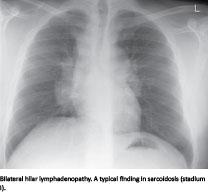

Sarcoidosis is an inflammatory, granulomatous disease. Its pathogenesis is unknown, but probably involves genetic predisposition as well as external factors [1]. Approximately 500 new cases are diagnosed in Denmark annually. Diagnosing sarcoidosis is challenging and includes radiological changes, clinical manifestations and paraclinical findings, including measurement of serum angiotensin-converting enzyme activity (s-ACE, peptidylpeptidase A). ACE has a number of metabolic effects; most notably it catalyses the modification of angiotensin I to angiotensin II, a potent vasoconstrictor [2] and inactivates bradykinin through the kallikrein-kininogen system [3]. It is also a potent pro-inflammatory modulator [4] secreted by activated cells of the monocyte-macrophage cell lineages, which are crucial in the process of granuloma formation. S-ACE is elevated in about 60% of sarcoidosis patients [5], but also in other granulomatous diseases like Gaucher’s disease and tuberculosis [6]. Though the level of s-ACE reflects the mass of granuloma in the body [7], the clinical use of s-ACE in monitoring disease activity is controversial, and recommendations differ between guidelines.